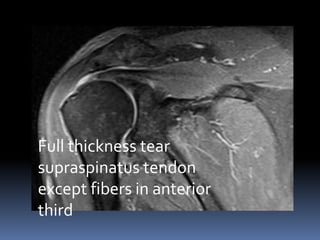

Full thickness tear

supraspinatus tendon

except fibers in anterior

third

 Complete tears of supraspinatus tendon are

accompanied by muscle atrophy and fatty

infiltration.

 These are important negative prognostic

factors for tendon repair and shoulder

arthroplasty.

 Muscle thickness using Fat occupancy ratio

and fatty infiltration of muscle can be

assessed on MRI.